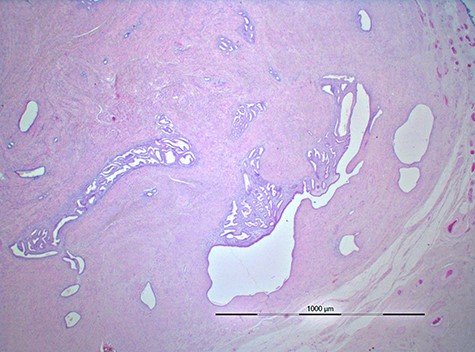

A 44-year-old multiparous woman (gravida 2, para 2), with a gynaecologic medical history of two caesarean sections at the age of 26 and 31, presented with a painful non-reducible mass in the right inguinal region without fever or other alarming symptoms. Two months prior to presentation a total laparoscopic hysterectomy was performed (without a salpingo-oophorectomy) because of menometrorrhagia. The intact uterus was removed vaginally and there were no complications in the postoperative phase. Histopathological analysis of the uterus was consistent with the preoperative diagnosis of adenomyosis. Additionally, two leiomyomas were found, one subserosal and one intramural, with a maximum diameter of 0.8 cm. Clinical examination revealed a palpable non-reducible regular mass of 3.0 ×2.0 cm in the right inguinal region near the round ligament of the uterus. Inguinal ultrasonography (US) showed a 2.2×1.4 cm hypoechoic solid mass suspicious for malignancy (Fig. 1). Because of the initial suspicion for malignancy, diagnostic workup also included an ultrasound of the abdomen and a chest X-ray, which showed no abnormalities. Laboratory investigations including white blood cell count, kidney and liver function were within normal ranges. Serology for Bartonella henselae antibodies was negative excluding cat-scratch disease. An ultrasound-guided biopsy was performed to obtain histology. Microscopic examination of the biopsy showed a leiomyomatous lesion, without signs of malignancy. The surgeon performed a resection of the mass. During the procedure, the mass was located proximal of the inguinal ligament and fixated in the inguinal ring. The mass was removed without any complications. Inspection of the specimen revealed a 1.8 × 1.8 × 1.5 cm white–gray regular mass surrounded by yellow–gray tissue. The histologic findings were consistent with extrauterine adenomyoma (Fig. 2). The patient was discharged within 24 h after surgery. The patient remained asymptomatic without any signs of recurrent disease after 1.5 years of follow-up.

Image of histopathology shows a well-circumscribed lesion composed of foci of benign endometrial glands and endometrial stroma surrounded fat and connective tissue.

The histopathology is that of a well-circumscribed lesion composed of foci of benign endometrial glands and endometrial stroma surrounded by hyperlastic smooth muscle bundles. In this case, the lesion was located in and surrounded by fat and connective tissue.